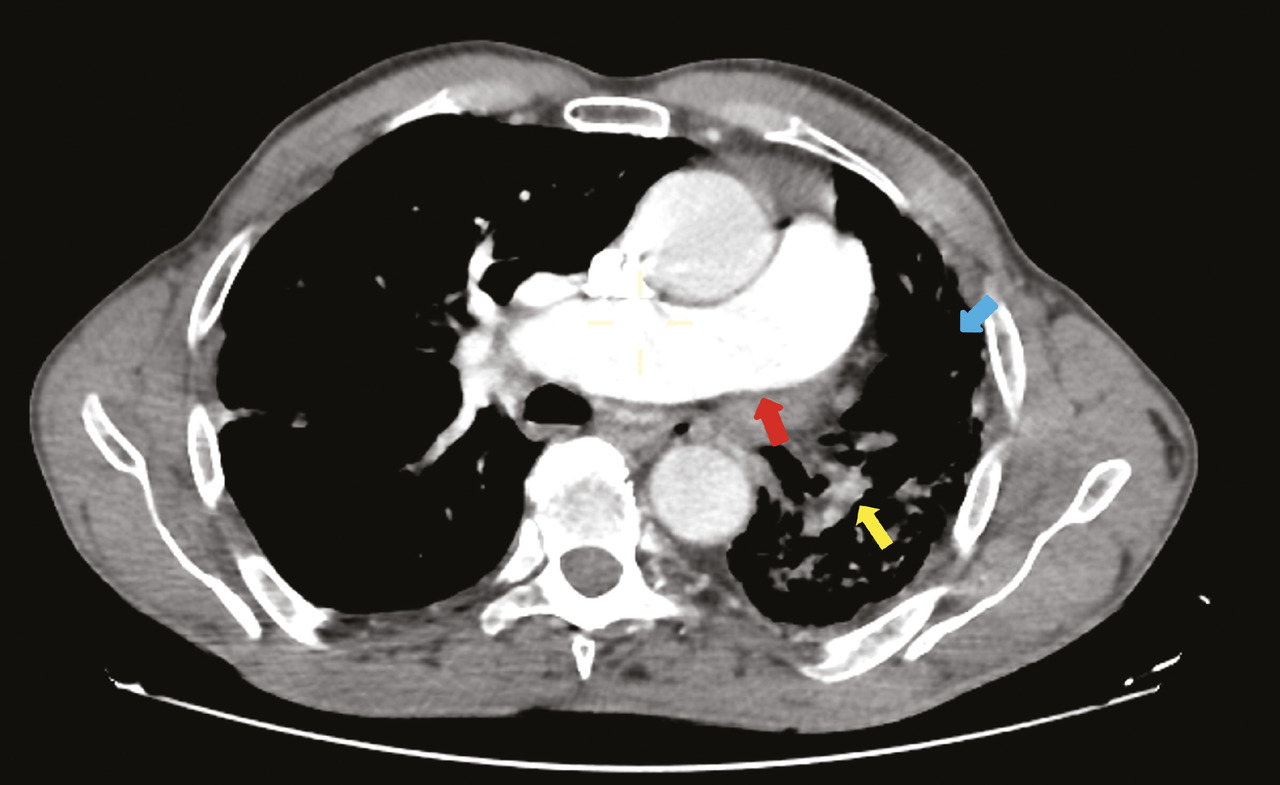

Un homme âgé de 66 ans, sans antécédents particuliers, est admis aux urgences pour la prise en charge d’un traumatisme thoracique minime. Une radiographie thoracique montre une asymétrie de taille des deux champs pulmonaires avec une déviation médiastinale vers la gauche (fig. 1). Un angioscanner thoracique montre une agénésie de l’artère pulmonaire gauche, une hypoplasie du poumon homolatéral et des lacérations vasculaires systémiques d’origine bronchique vascularisant le poumon gauche (fig. 2).